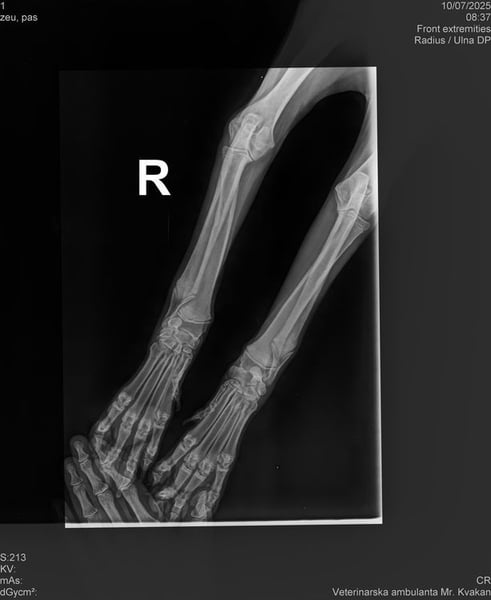

Bemerkungen: Unda humpelt ein wenig. Es sind Röntgenbilder vorhanden und darauf ist nichts ungewöhnliches zu erkennen. Momentan bekommt sie Schmerzmittel und die Angelegenheit wird Tierärztlich beobachtet

Die kleine Unda kam aus einer Romasiedlung. Wir konnten beobachten, dass sie ein wenig humpelt. Aus diesem Grunde durfte Unda im Tierheim einziehen. Sie wird nun tierärztlich überwacht. Die angefertigten Röntgenbilder lassen nichts ungewöhnliches an ihren Beinchen erkennen. Momentan bekommt Unda Schmerzmittel und die Angelegenheit wird weiterhin tierärztlich beobachtet